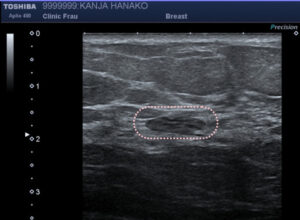

低エコー域とは

はっきりとしたしこり(腫瘤)としては確認できないが、正常の乳腺とはいえない影があること。